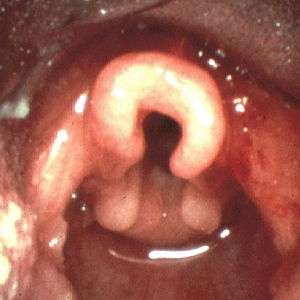

Omega shaped epiglottis, seen in laryngomalacia | |

In infantile laryngomalacia, the supraglottic larynx (the part above the vocal cords) is tightly curled, with a short band holding the cartilage shield in the front (the epiglottis) tightly to the mobile cartilage in the back of the larynx (the arytenoids). These bands are known as the aryepiglottic folds. The shortened aryepiglottic folds cause the epiglottis to be curled on itself. This is the well known "omega shaped" epiglottis in laryngomalacia. Another common finding of laryngomalacia involves the posterior or back part of the larynx, where the arytenoid cartilages or the mucosa/tissue over the arytenoid cartilages can collapse into the airway and cause airway obstruction.